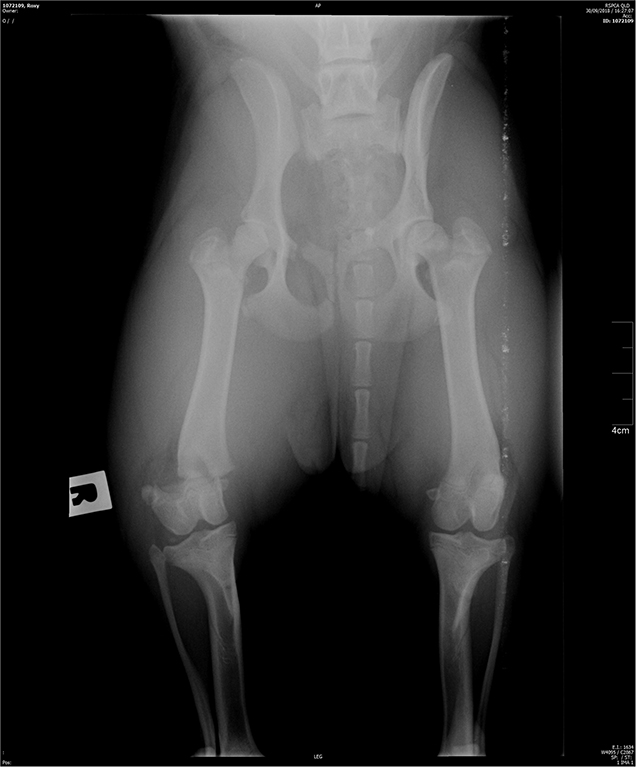

Roxy, a 7-month-old English Staffordshire Bull Terrier cross was surrendered to the RSPCA with a right hind distal femoral fracture.  Her injury was sustained when she jumped out of the owner’s car window while in transit.

Roxy X-ray